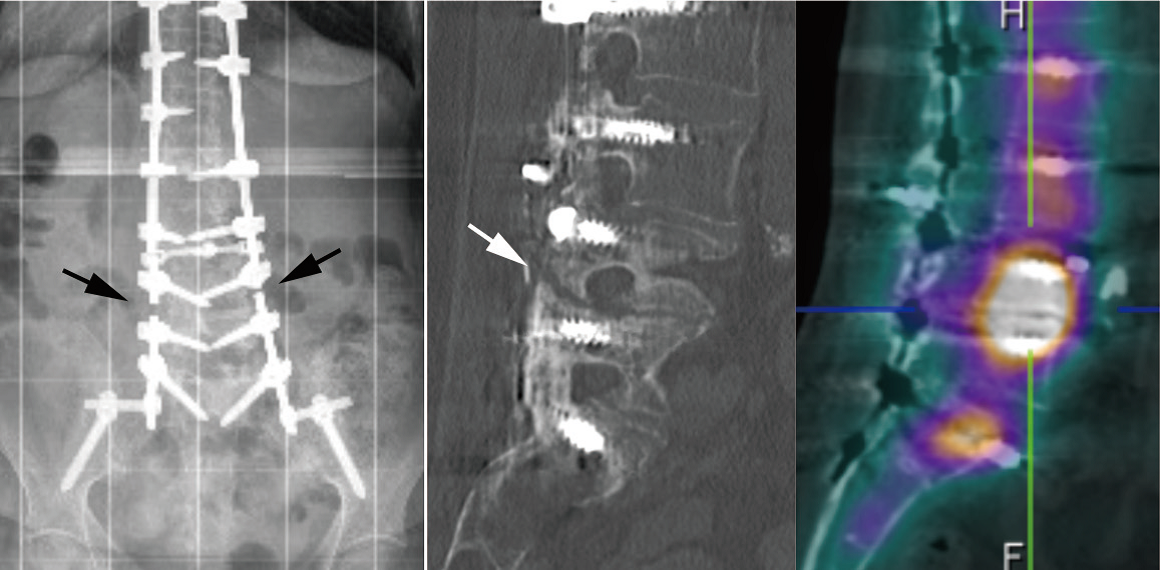

不融合与内固定棒断裂

如果术后患者在随访过程中出现疼痛,并且X光片显示内固定棒断裂,则应高度怀疑脊柱出现不愈合的情况。在判断节段不融合时,应不断强调内固定棒在单一节段上发生断裂,并不代表仅存在该节段的脊柱不融合,应警惕多节段不融合的风险。所有脊柱节段均应在影像学上进行仔细检查,并在术中进行探查,以避免多次的翻修手术。文中,作者还特别强调了Ponte截骨在应用此类患者时的注意事项。Ponte截骨术在当通过有力的加压对节段性后凸畸形进行矫正时,前方骨赘可能会出现破裂,导致前方狭窄的椎间隙张开。此时,必须通过前路支撑与植骨来稳定这些节段,以防止术后矫正丢失与不融合情况的发生。如果已经发生,则建议使用OLIF进行前路的支撑融合。

脊柱不融合内固定棒断裂

Ponte截骨使狭窄的间隙在前方张开,后期可能缺乏良好的前柱支撑出现不融合